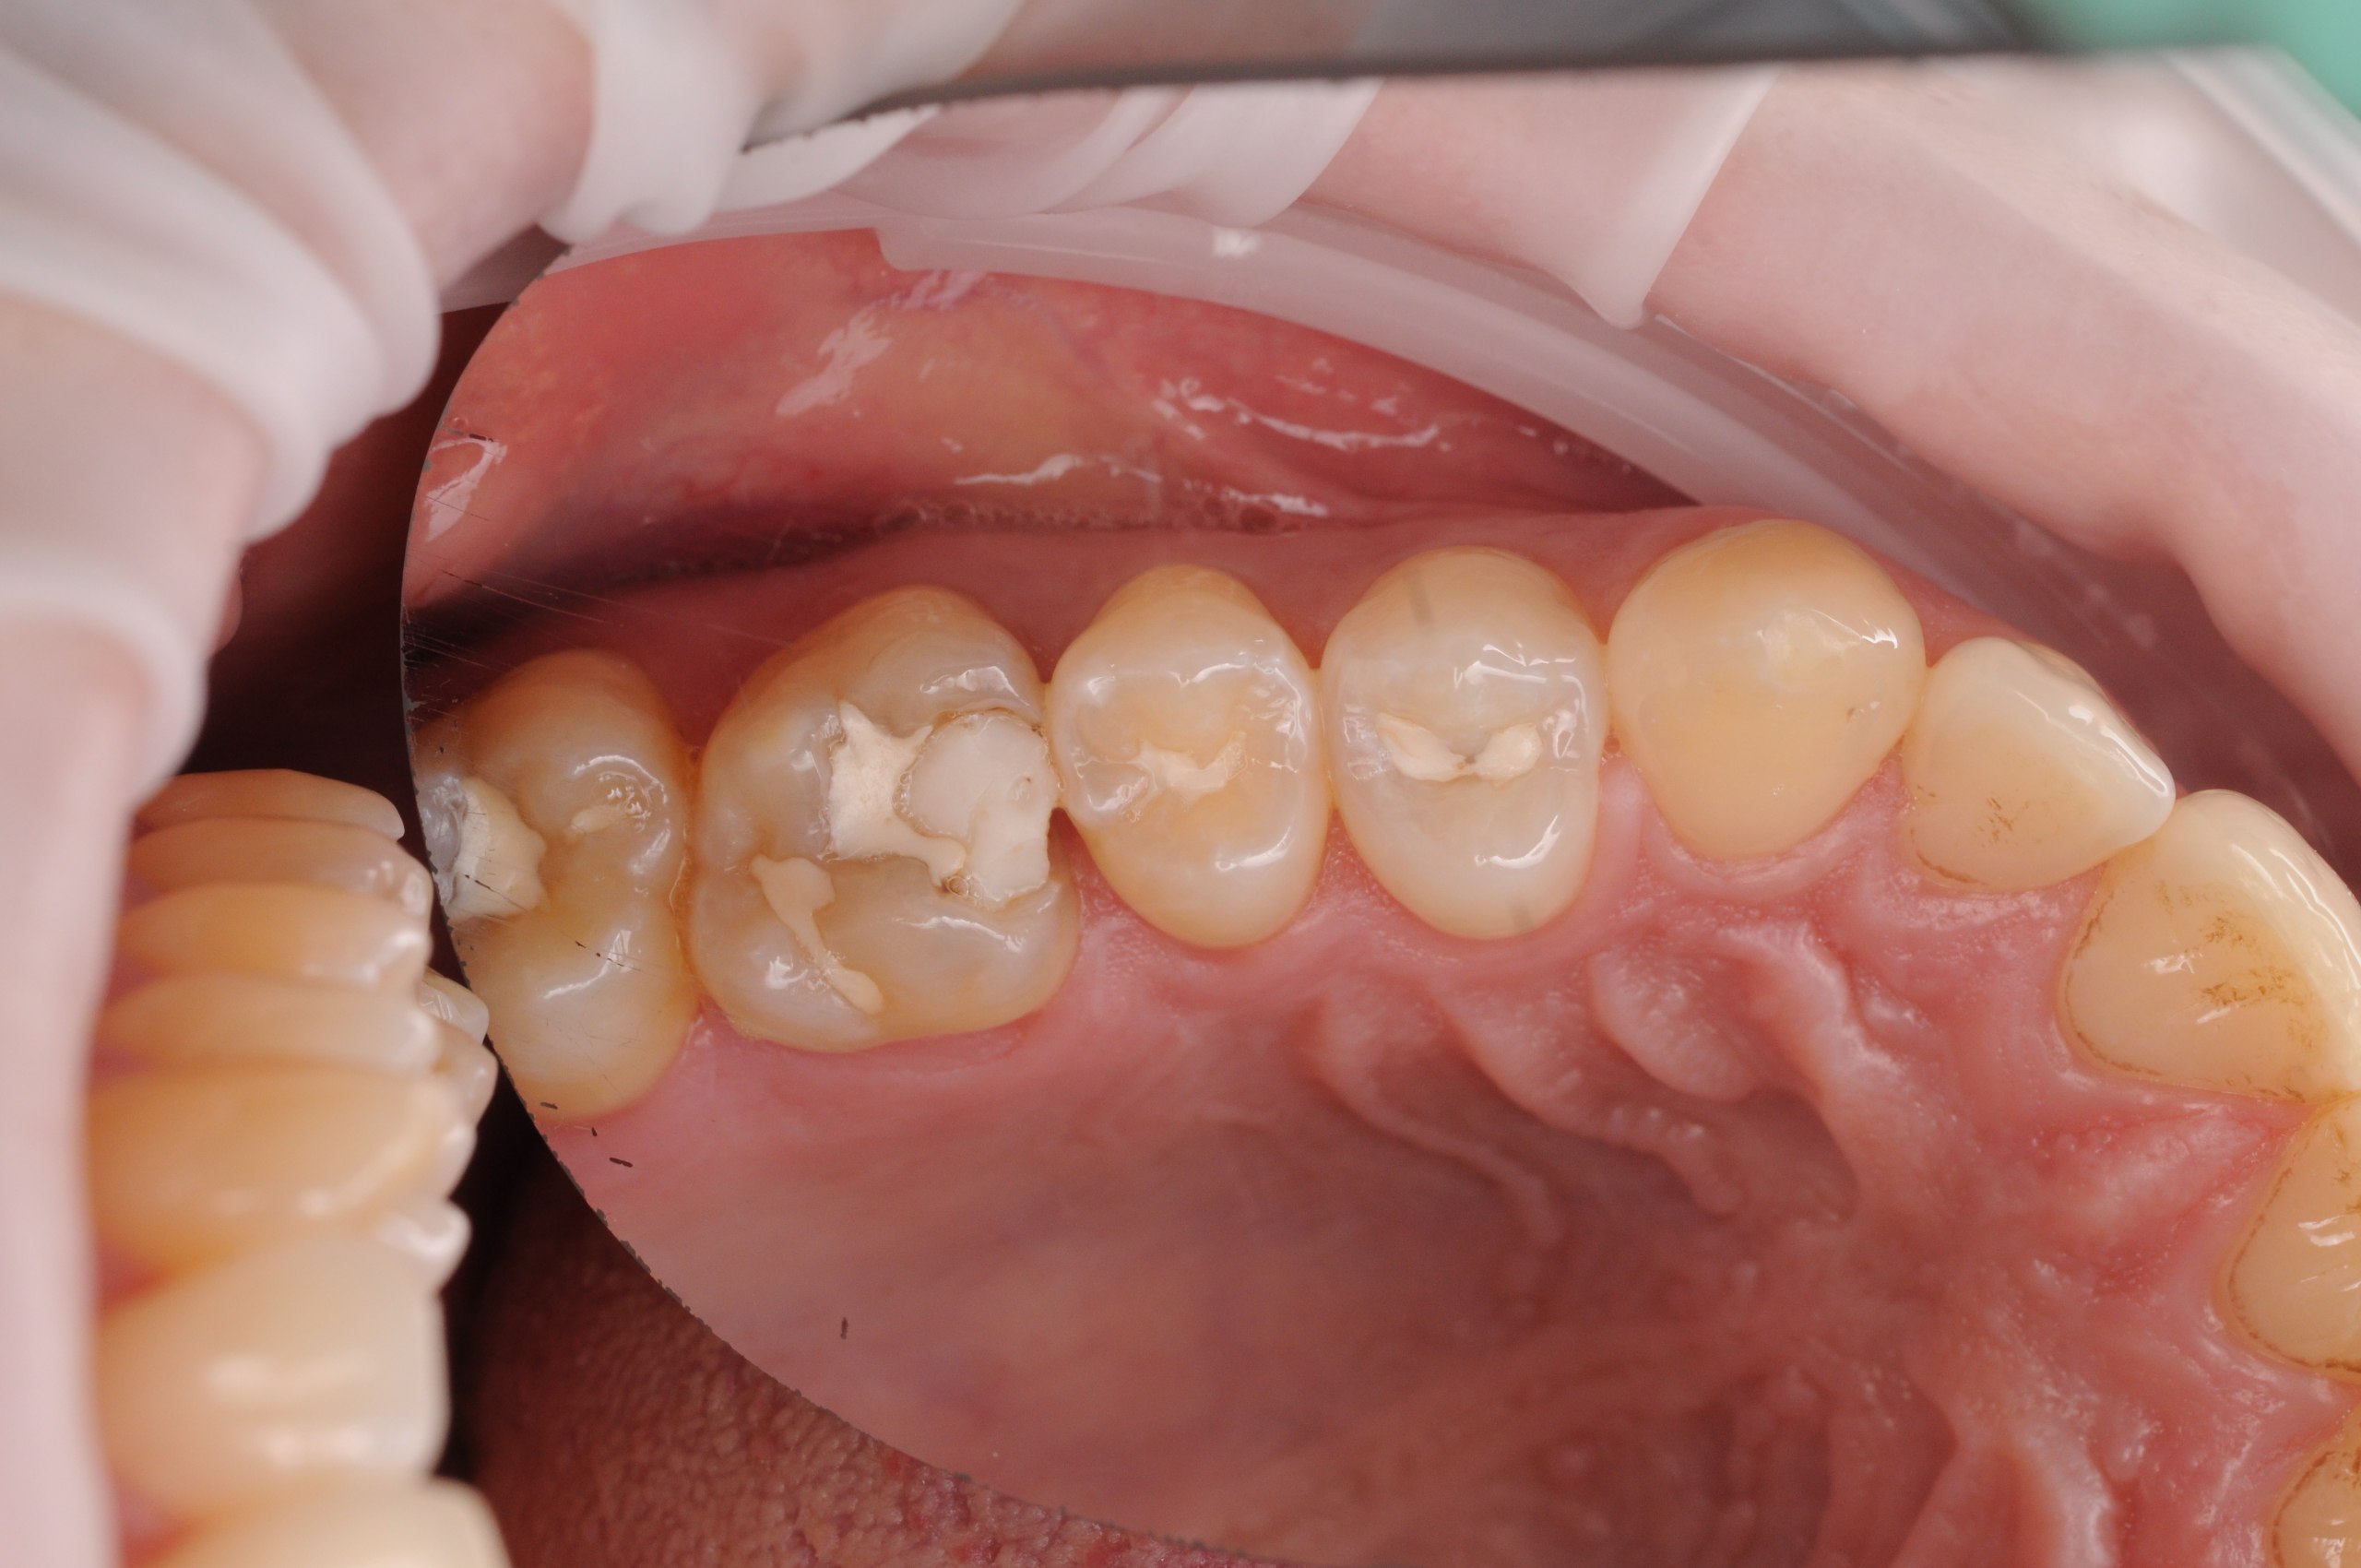

Během vyšetření byla na povrchu zubu vidět pouze malá skvrna pigmentu, ale při bližším vyšetření bylo zjištěno významné množství zubního kazu uvnitř. I přes to, že kaz nebyl zvenčí vidět, pronikl hluboko do struktury zubu. Bylo provedeno odstranění zkažené části a obnovení struktury a funkce zubu. Materiál plomby byl pečlivě vybrán tak, aby odpovídal přirozené barvě zubu a zajišťoval estetický výsledek. Tento případ ukazuje důležitost důkladného vyšetření a včasné řešení kazu.

1. Před

2. V průběhu

3. V průběhu

4. Po

5. Po